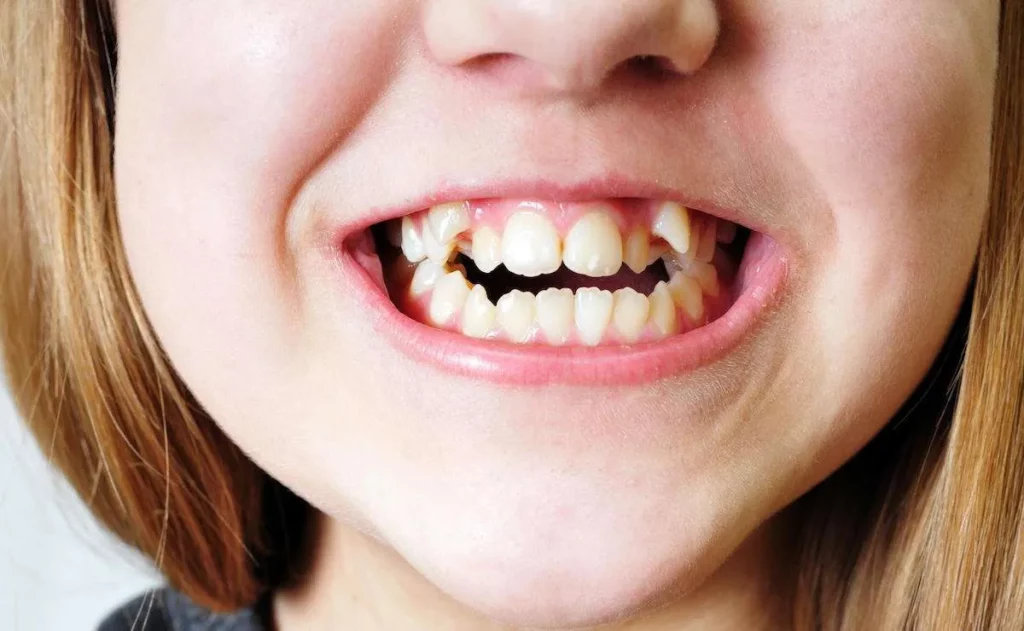

Le remodelage du sourire s’adresse à toutes les personnes souhaitant :